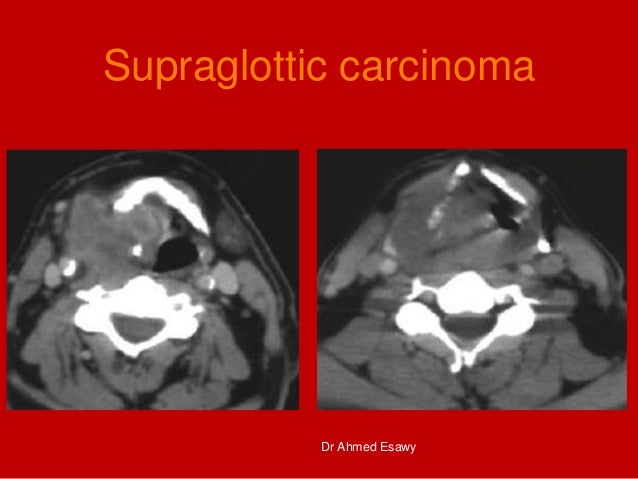

13. 13. Supraglottic carcinoma Dr Ahmed Esawy

14. 14. Coronal construction for craniocaudal invasion and paraglottic extention Axial CT for lymph nodes Dr Ahmed Esawy

15. 15. Supraglottic carcinoma Dr Ahmed Esawy